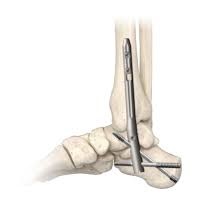

Am Tag selbst werde ich am Morgen aufgenommen, dann folgt eine Blutentnahme und das Gespräch mit der Anästhesie. Um 13:00 Uhr beginnt die Operation, die mehrere Stunden dauern wird. Geplant ist ein retrograder tibio-talocalcanealer Nagel (TTC). Konkret bedeutet das, dass eine Titanstange vom Fersenbein bis zum Schienbein eingesetzt wird, um die Stabilität zu sichern. Die beiden betroffenen Gelenke, das untere Sprunggelenk (USG) und das obere Sprunggelenk (OSG), werden dauerhaft versteift. Die Beweglichkeit der Sprunggelenke ist damit weg, aber da ich seit über einem Jahr ohnehin nicht mehr abrollen kann, wird die Umstellung weniger drastisch ausfallen, als es klingt.

Der Fuss wird neu positioniert, und der Raum, in dem einst mein Sprunggelenk war, das durch die Staphylokokken-Infektionen praktisch zerstört wurde, wird mit Knochenmaterial aufgefüllt. Dieses wird entweder aus meinem Becken entnommen oder, falls nötig, aus einer Knochenbank bezogen. Eigenknochen hat den Vorteil, dass mein Körper ihn in der Regel besonders gut akzeptiert, kein Risiko eines “biologischen Missverständnisses”.